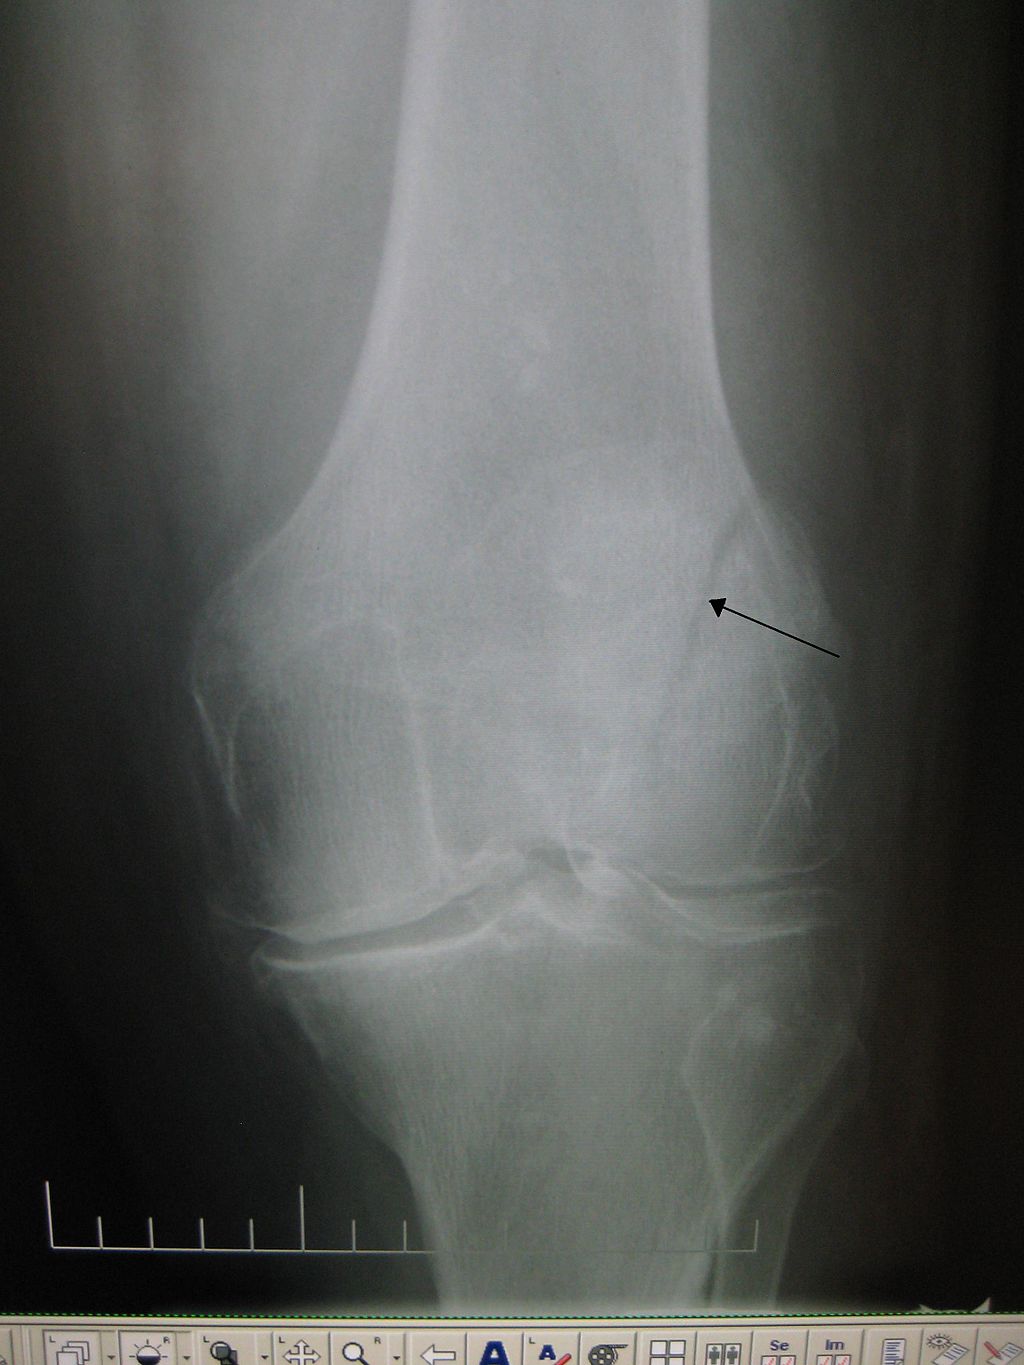

How Long Do Knee X Rays Take . This can help them diagnose osteoarthritis. The femoral and tibial condyles should be symmetrical, with the head of the fibula slightly. The purpose of knee radiographs is to assess the bony structure of the knee and specifically to define the presence of fractures and also to assess for degenerative disease within. Knee arthritis can affect one side of the joint more than the other.

The femoral and tibial condyles should be symmetrical, with the head of the fibula slightly. Knee arthritis can affect one side of the joint more than the other. The purpose of knee radiographs is to assess the bony structure of the knee and specifically to define the presence of fractures and also to assess for degenerative disease within. This can help them diagnose osteoarthritis.